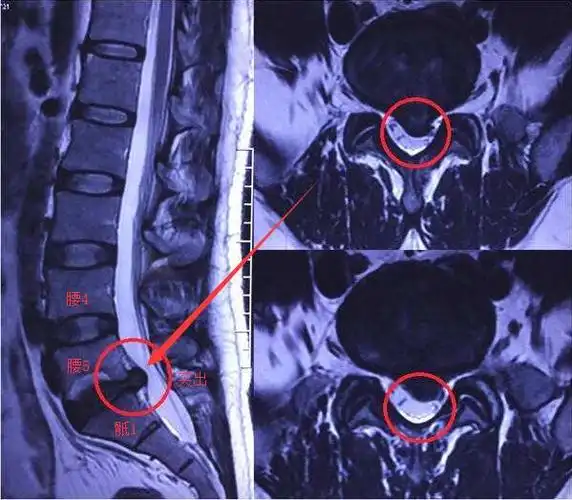

腰5骶1是一个腰椎间盘突出的好发部位.骨科无锡虹桥医院